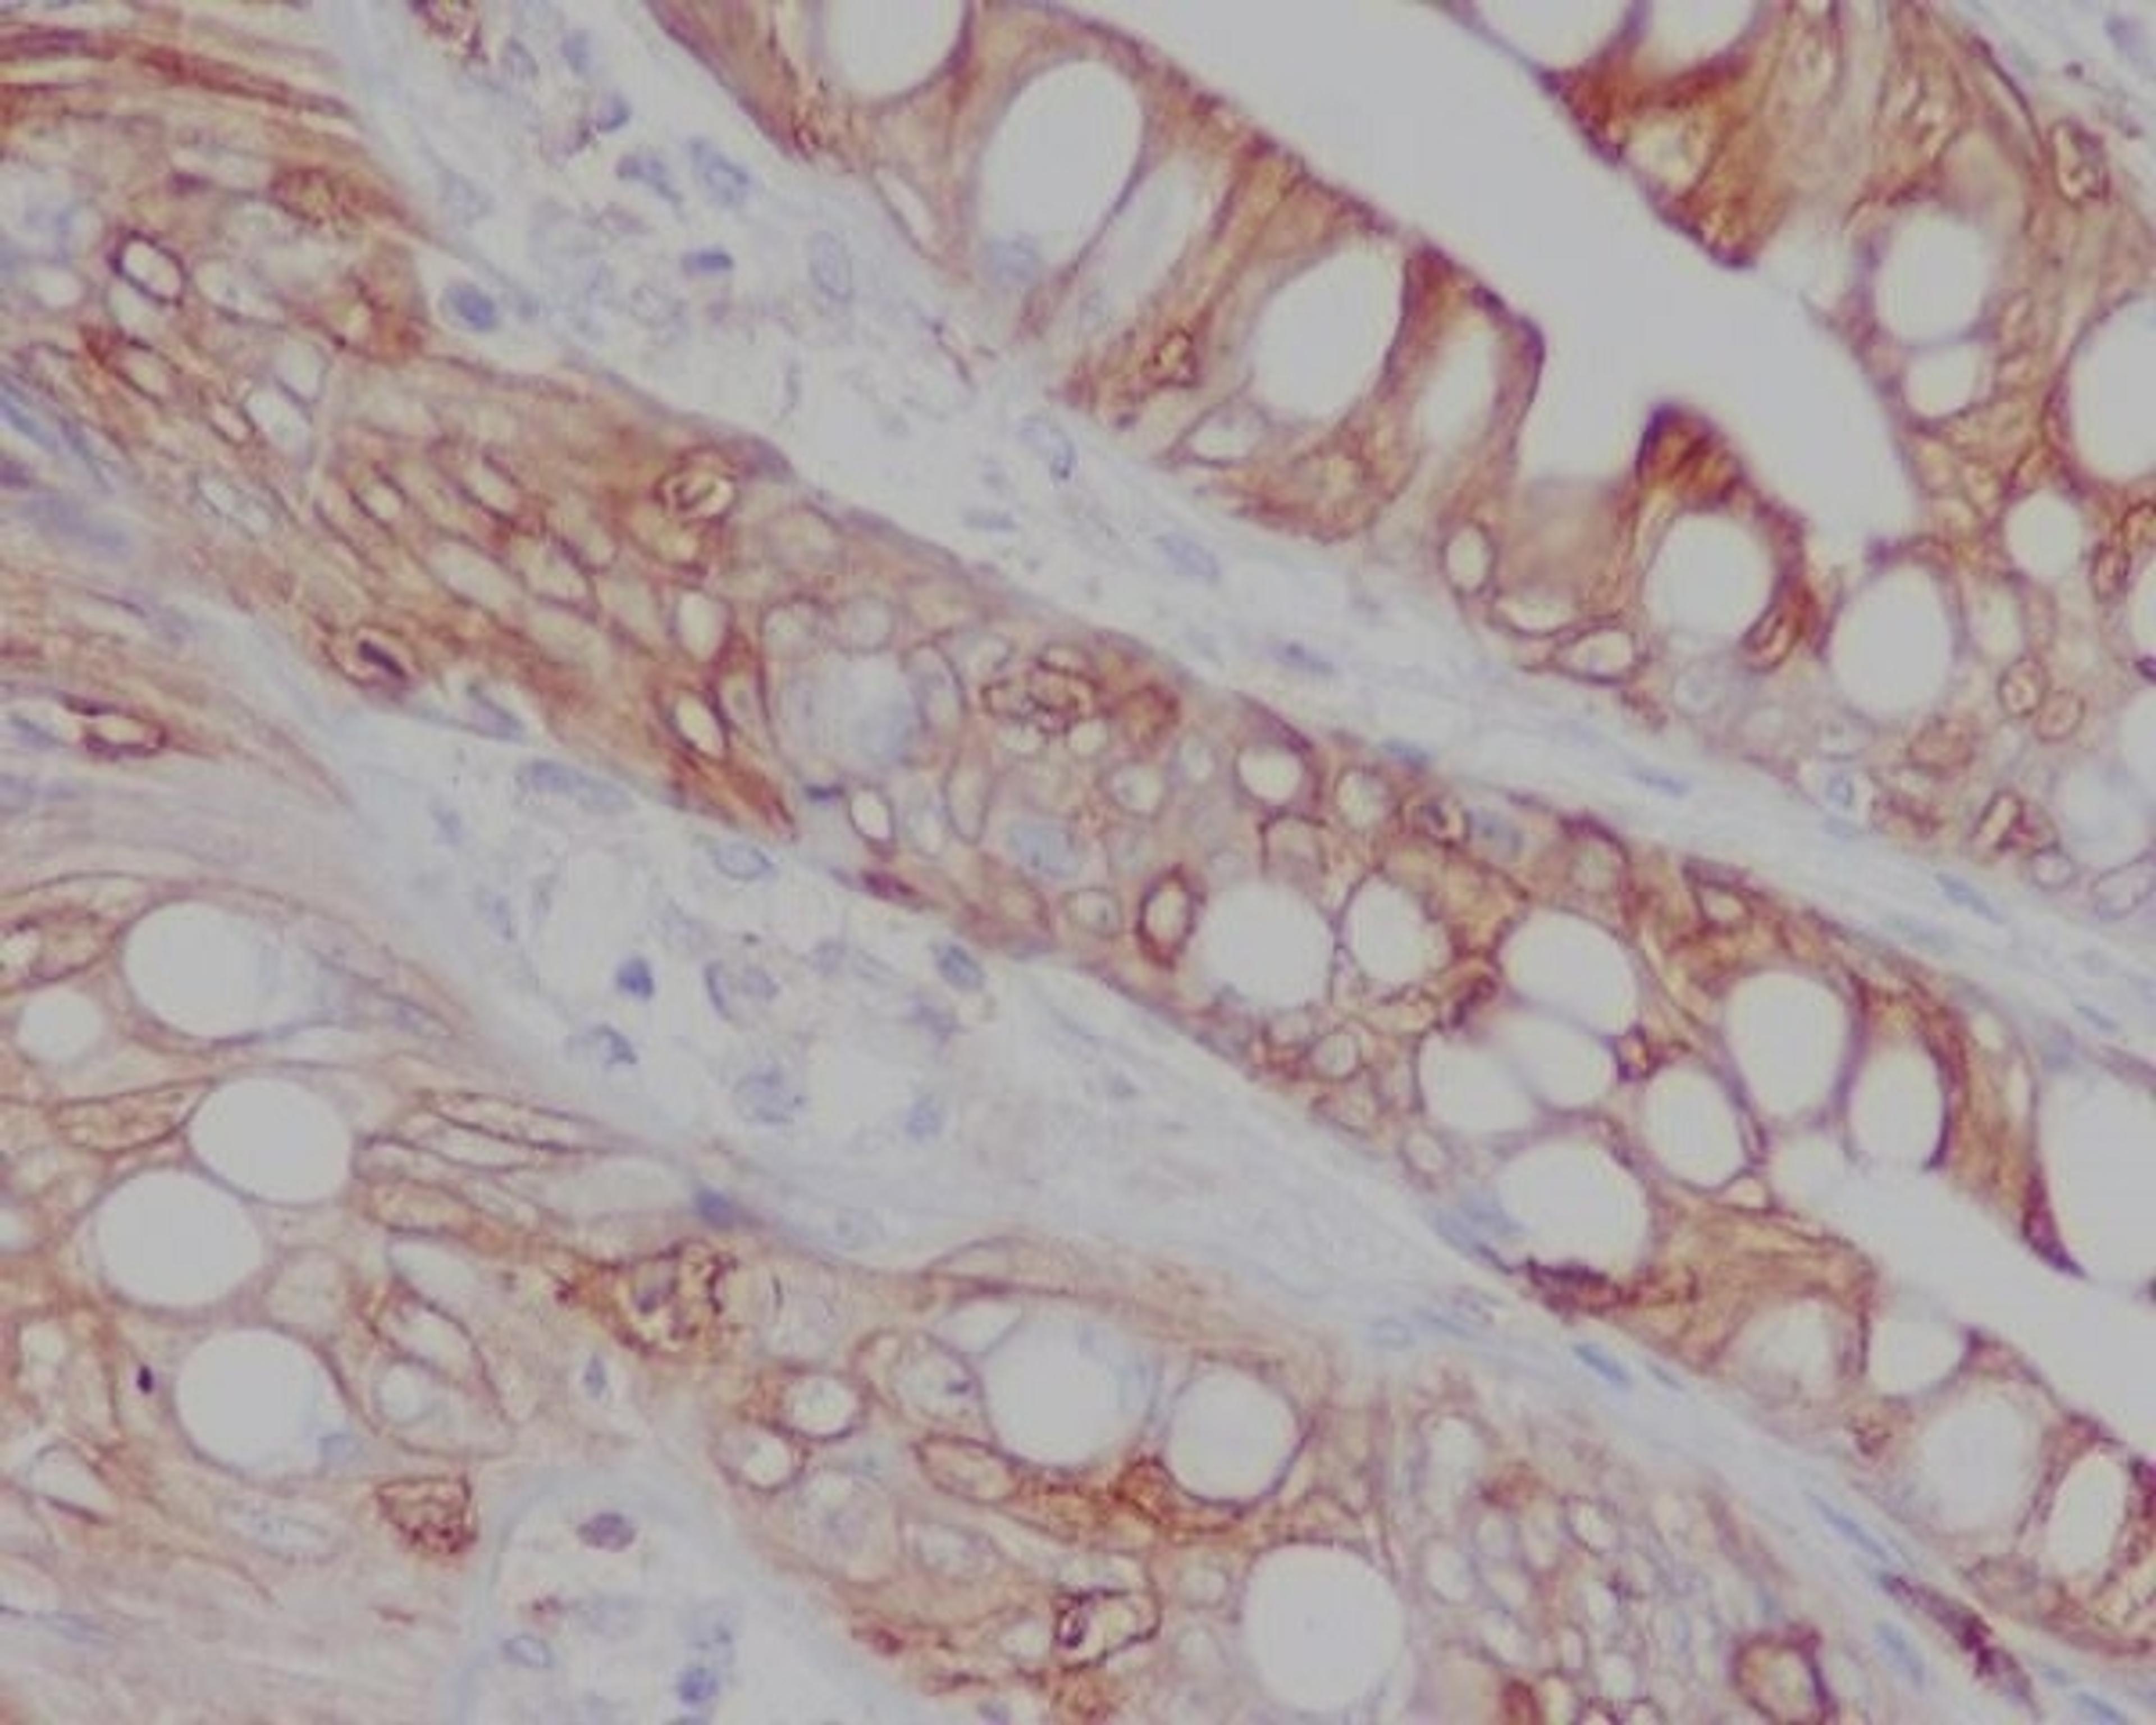

Boster Bio Anti-CD8 CD8A Rabbit Monoclonal Antibody catalog # M02236-1. Tested in IF, IHC, ICC, WB applications. This antibody reacts with Human.